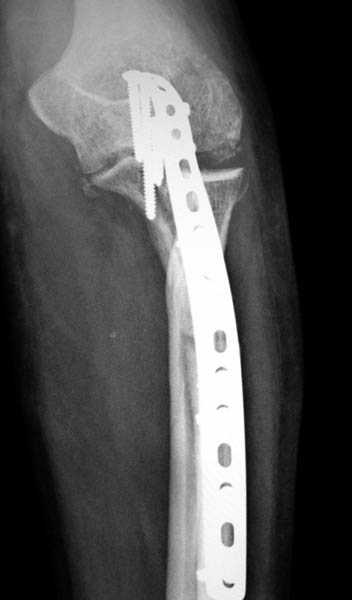

Здесь выставлены несколько случаев и варианты фиксации локтевого отростка, некоторые в комбинации с другими переломами.

3 вариант

перелом с capitelum humerus и проксимальной трети улна